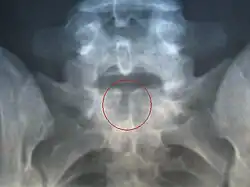

Spina bifida occulta

Il représente la forme mineure et la plus répandue de la malformation. Il n'existe pas d'ouverture ni de déformation cutanée dans la région lombo-sacrée (la peau en regard des anomalies peut rester normale ou porter une zone très poilue, un nævus ou un hémangiome, voire une petite dépression du derme). Pourtant la radio révèle une fermeture incomplète de la partie postérieure de la vertèbre. Dans cette forme, la fente reste très limitée, et la moelle spinale n'en dépasse pas (il n'y a pas de protrusion). Les conséquences de cette forme sont variables, mais la plupart du temps asymptomatiques[5].